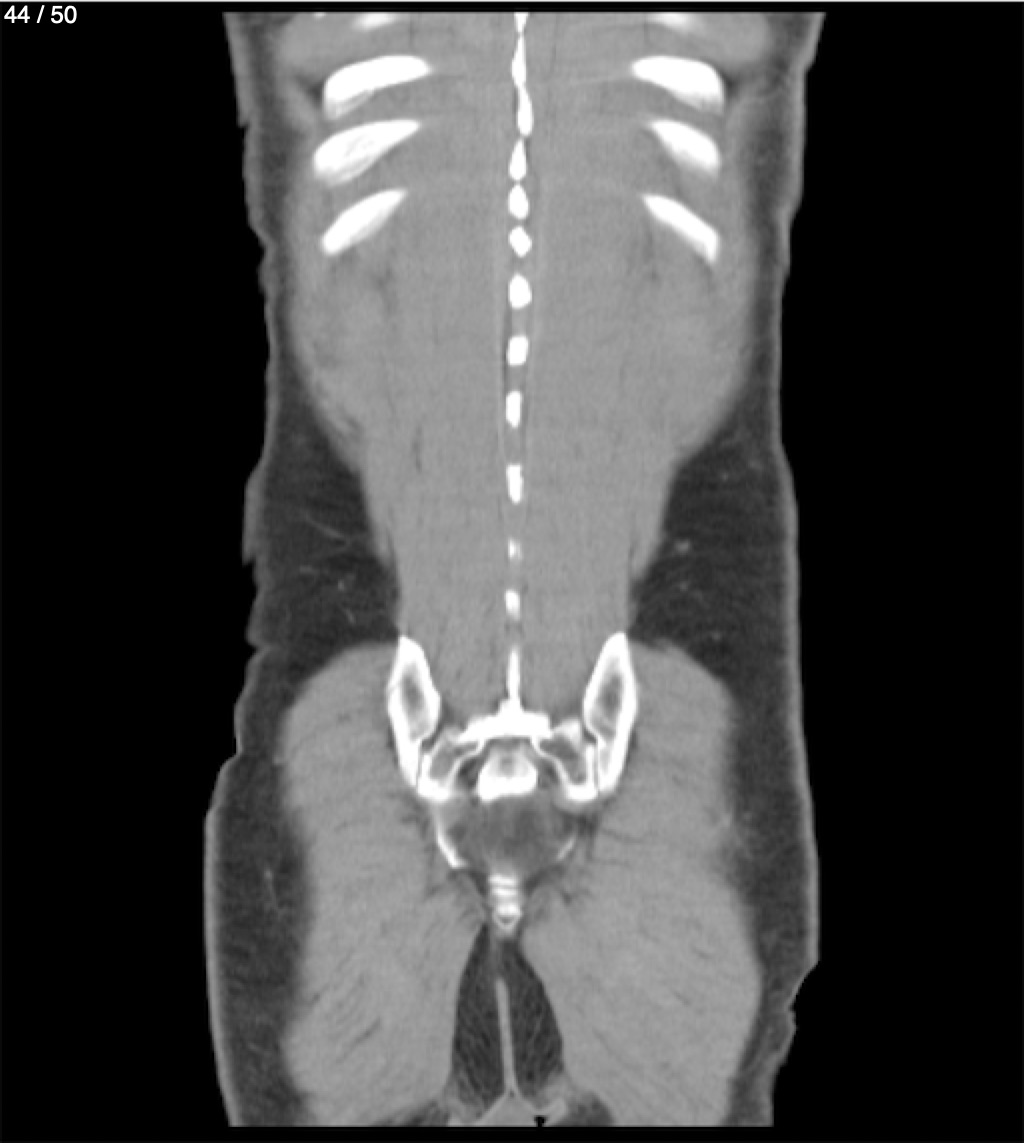

Alonso Victorio Ruiz 62A - T.C Abdomen Syc